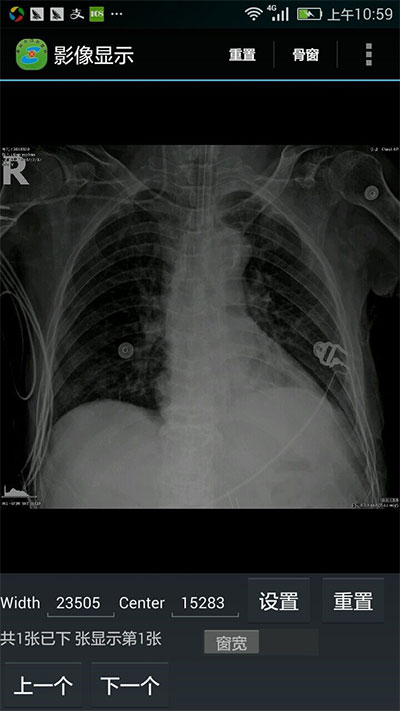

通过技术人员近一年的开发实践,中心医院掌上医疗项目开发完成,实现了病人全信息的查询功能:能展示病人的体温单、医嘱单、入院记录、病程记录、手术记录、出院记录、检验检查报告单、医学影像、窗位变换等。

窗位变换:

窗位变换前 窗位变换后

湖州中心医院一直致力于医疗信息化建设,加快医生诊断、检查流程,提高病人就医体验,为了使医生能够随时了解并掌握病人的实时信息,医院决定引入掌上医疗,并为医生配备了业务手机,方便医生及时获取病人的诊疗数据。但dicom数据的读取一直以来难以移植到移动端,尤其图像处理这一部分的开发是比较有难度的,目前业界在移动端上连接pacs和展示医学影像的控件就数leadtools比较成熟,能够在手机上显示医学影像文件、更改窗位、连接pacs系统、显示病人信息。大大减少开发难度,节省开发成本。